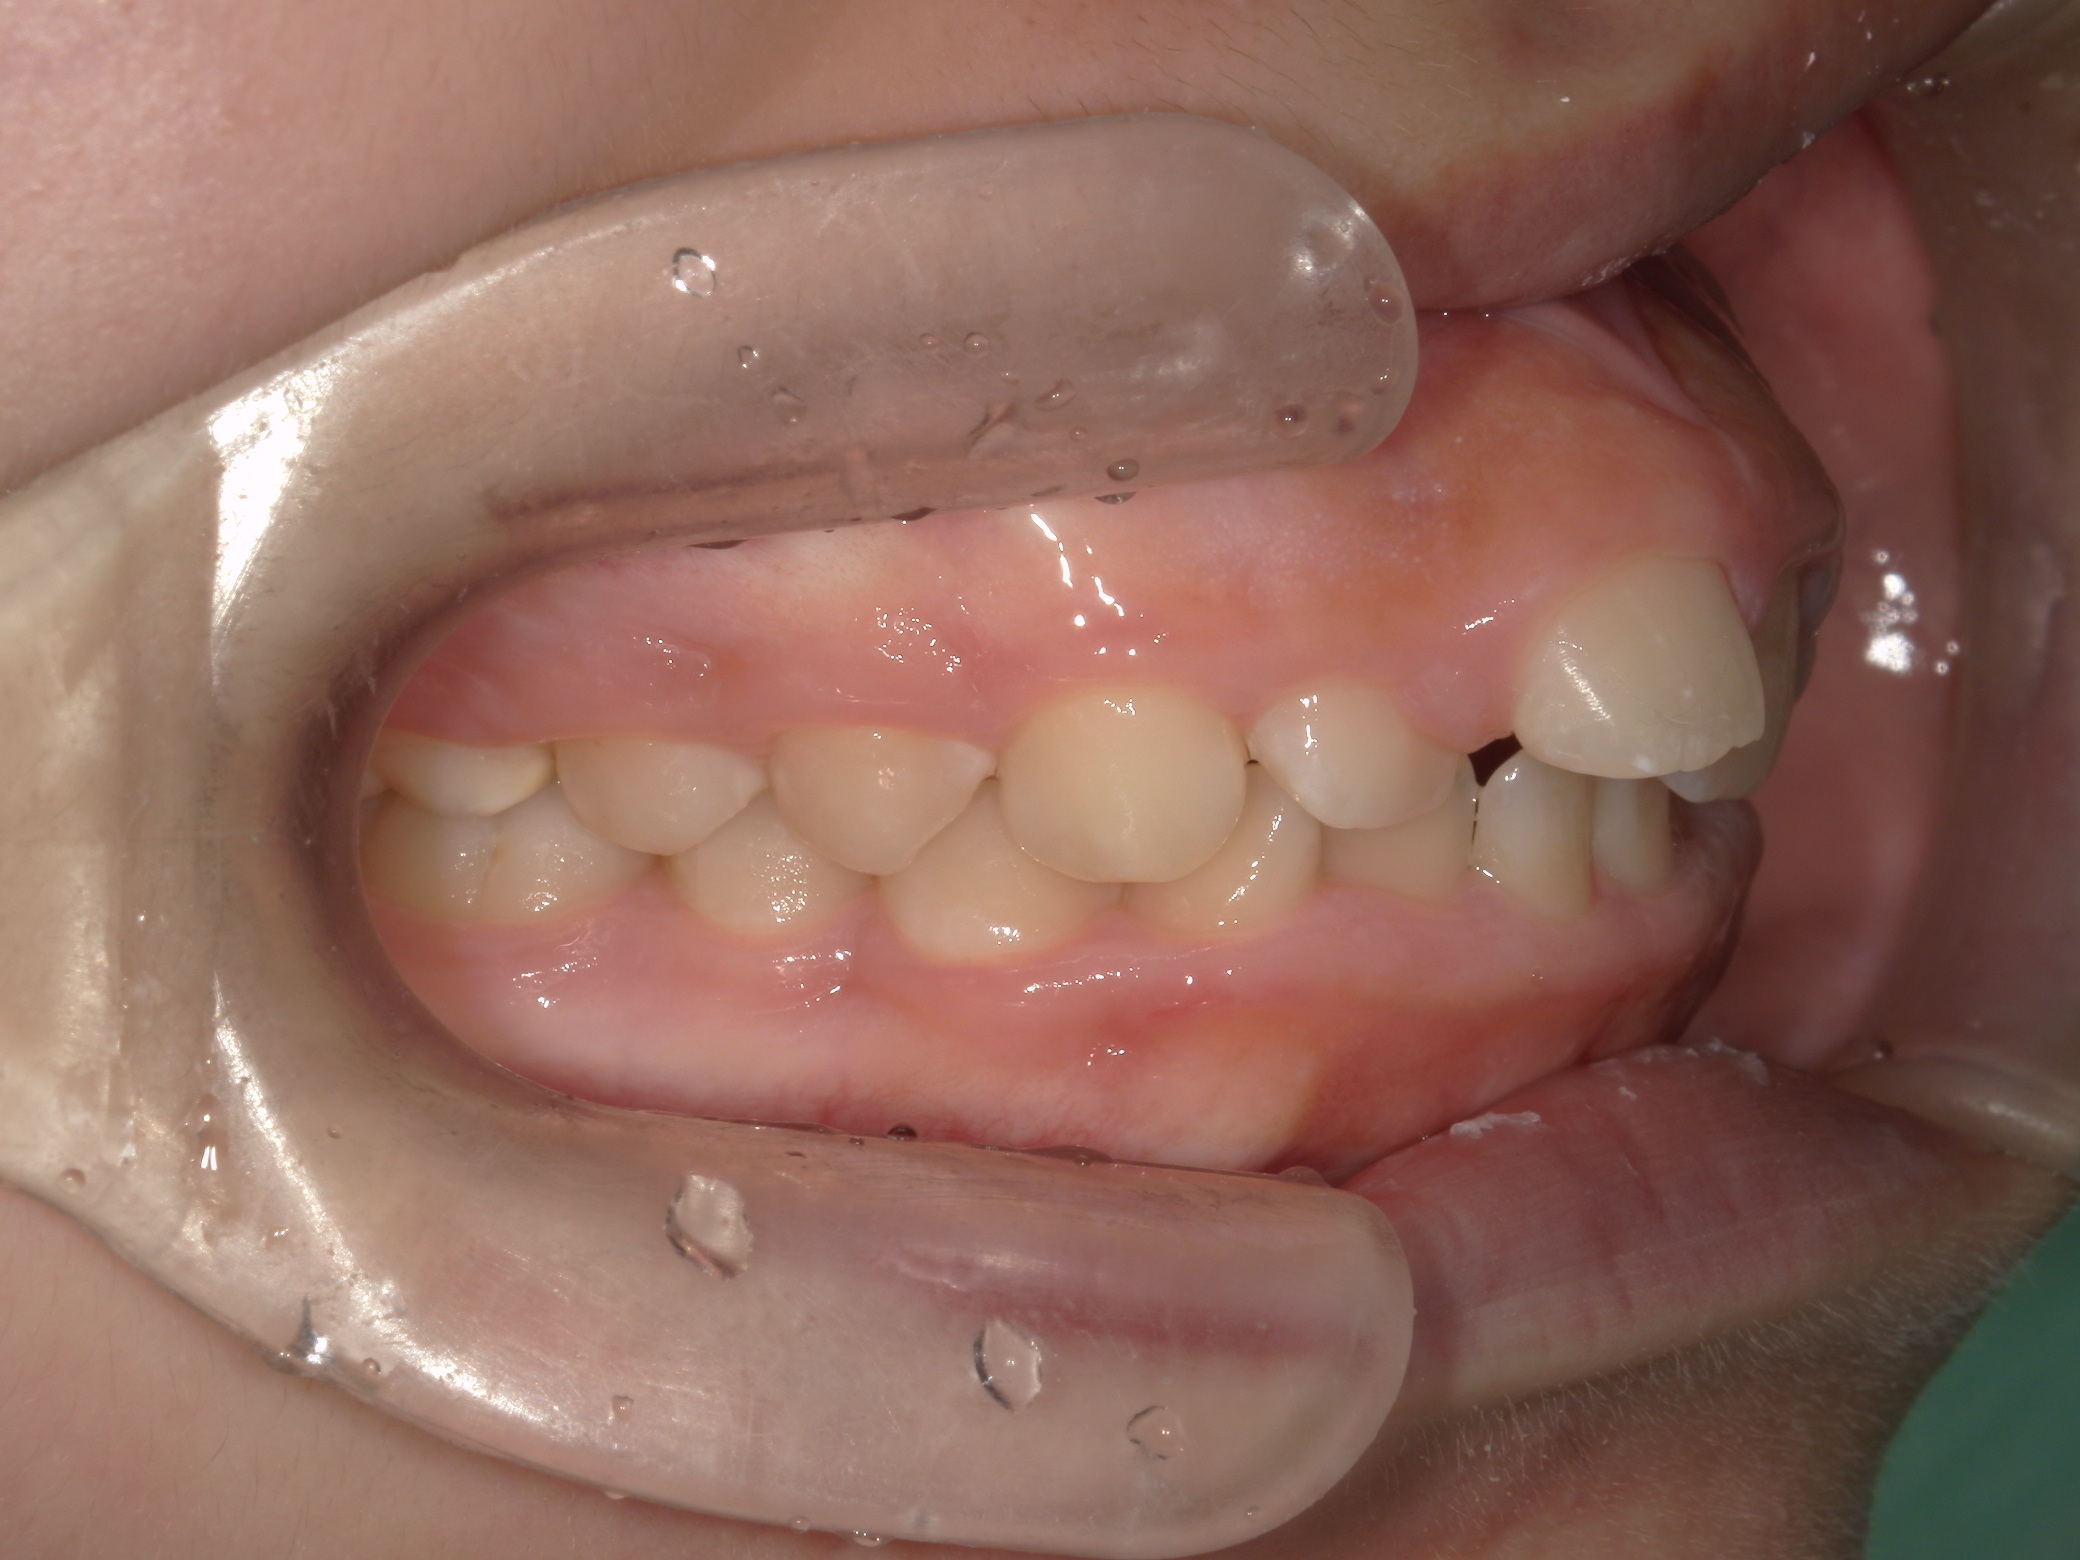

【中学生】インビザライン矯正 上顎前突(出っ歯)を改善

中学生以降

インビザライン フル

出っ歯

過蓋咬合

非抜歯

2期治療のみ

Before

After

治療期間

1.7年

治療開始

14歳歳

種類

インビザライン矯正

使用装置

インビザラインフル ディスキング併用

コメント

しっかり装着してくれて 予定通りに治療が終了しました。